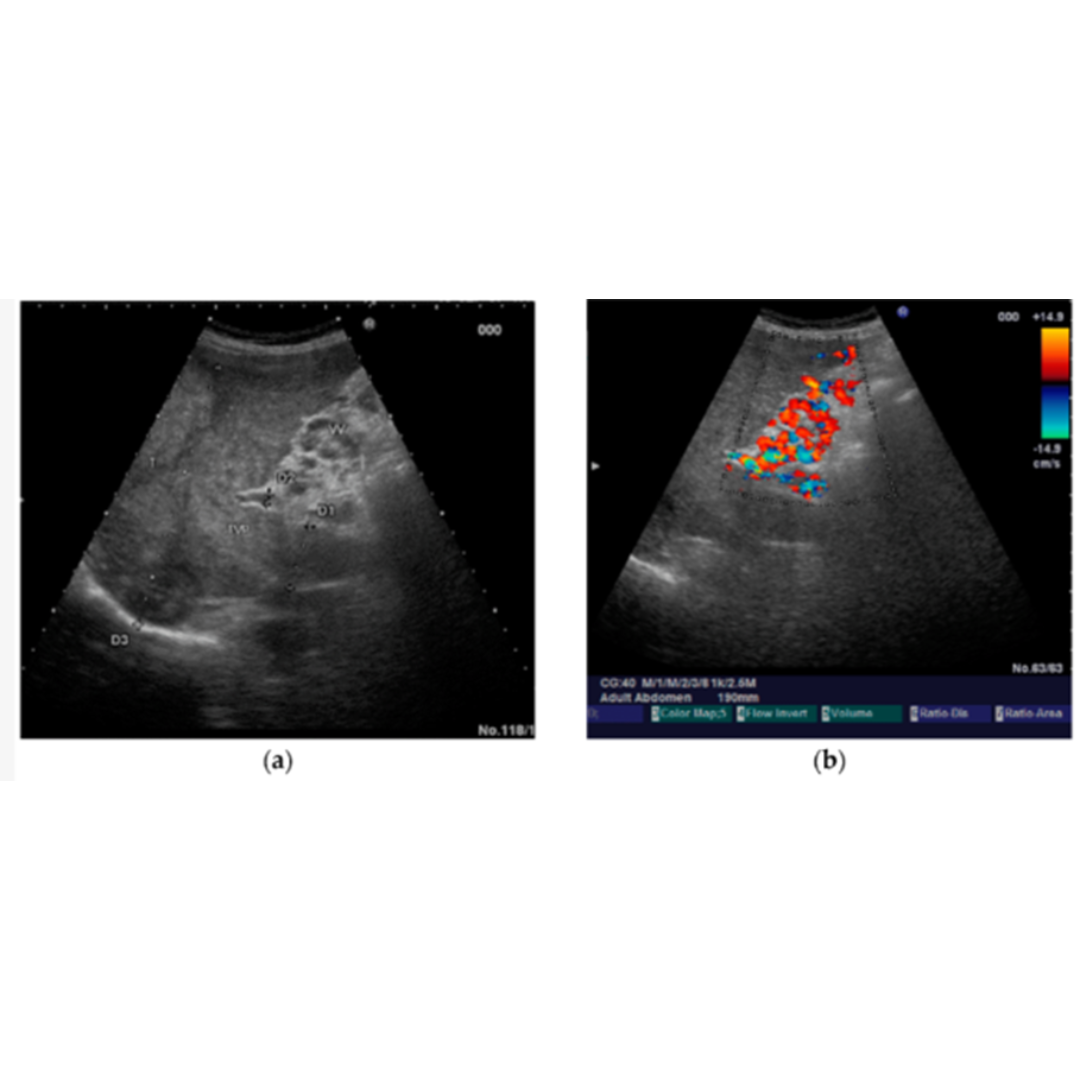

Cavernomatosis Portal

Es una enfermedad poco frecuente causada por trombosis en la vena porta que puede darse por invasión tumoral (hepatocarcinoma), por cirrosis avanzada donde el flujo hepático se ve severamente disminuido hasta trombosarse.

En estos casos se desarrolla una circulación colateral alrededor de una porta con calibre reducido y tromobosada, pudiéndose ver a nivel intra como extrahepático (figura 17 y 18 ).

Figura 17: Transformación portal cavernosa, se observan en modo B múltiples vasos serpiginosas libres de eco que reemplazan a la vena porta en hilio hepático, viéndose presencia de flujo venoso dentro de los cavernosas. (5)

Figura 18: Ramas venosas sinuosas en hilio hepático, con porta trombosada. Doppler color identifica flujo dentro de los vasos.